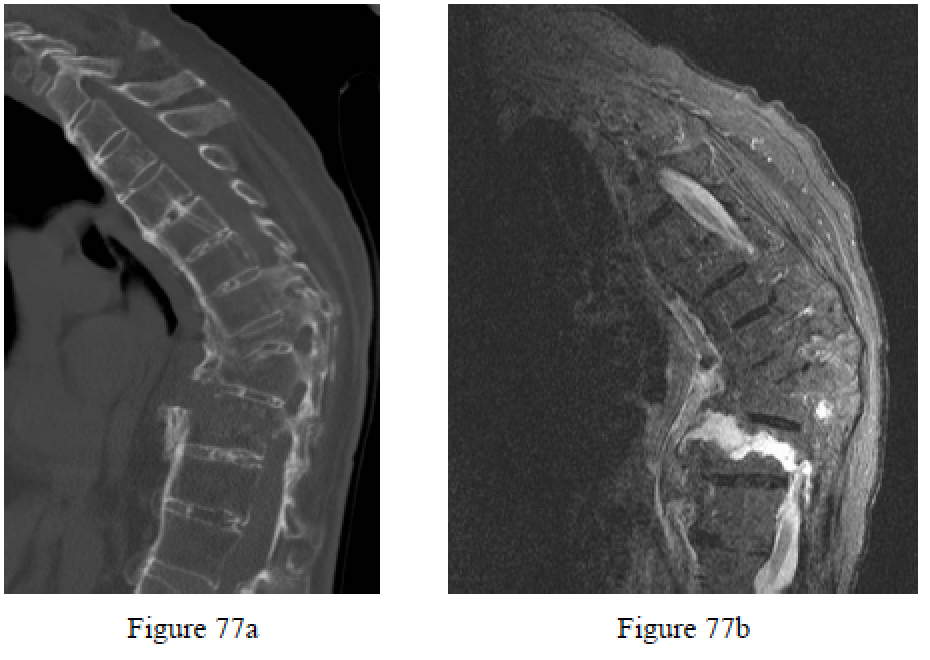

Question 77

Figures 77a and 77b are the CT scan and MR image of a 62-year-old woman who fell at home. She has severe back pain and describes an extension injury. Examination reveals severe thoracic kyphosis, but motor and sensory functions are normal. What is the most appropriate treatment?